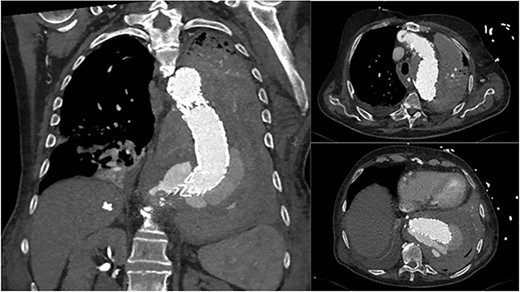

An 84-year-old male was admitted with sigmoid diverticulitis with a contained perforation in the colonic mesentery. His medical background included open thoracoabdominal aortic aneurysm repair 15 years prior, and chronic obstructive pulmonary disease. He was managed nonoperatively with intravenous antibiotics. On day 5 of admission, he acutely deteriorated with hypotension, tachypnoea and 200 mL of fresh haematemesis. Chest X-ray indicated opacification of the left lung, presumed to represent aspiration of haematemesis (Fig. 1). The patient received blood transfusion and proceeded to urgent gastroscopy, which identified old blood in the stomach and a Dieulafoy lesion, which was clipped. Post-procedure, the patient remained haemodynamically normal in intensive care, however had worsening opacification of his left lung on X-ray. The patient underwent bronchoscopy, with extraction of a further 200 mL of clot from the bronchial tree. In light of his vascular history, the patient proceeded to computed tomography (CT) angiography, which indicated a large Type 1 endoleak at the inferior margin of his thoracic aortic endograft, with a large left haemothorax and complete collapse of the left lung (Fig. 2). In the context of his comorbidities with active deterioration, the patient was palliated.

Coronal and axial CT thoracic aortogram indicating large Type 1 endoleak with large left haemothorax.